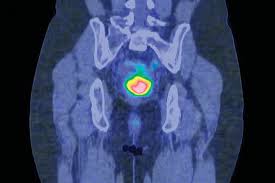

Clinical Review Cervical Cancer Gponline from cached.imagescaler.hbpl.co.uk Cervical cancer in and of itself really the most common warning sign or symptom from that really is abnormal bleeding. Chemotherapy — powerful medicines, in pill form or injected into the veins. Cervical cancer is a type of cancer that develops in a woman's cervix (the entrance to the womb from the vagina). Tiny changes begin in epithelial cells. Cervical cancer usually takes years to develop. Most cervical cancer is caused by a virus called human papillomavirus, or hpv. This is a common sexually transmitted virus that can cause infections. The american joint committee on cancer (ajcc) tnm classification and the international federation of gynecology and obstetrics (figo) staging system for cervical cancer are provided below.

Read about screening, using pap smears and testing for the hpv virus, which causes most cases. If you log out, you will be required to enter your. Various strains of the human papillomavirus (hpv), a sexually transmitted infection, play a role in causing most cervical cancer. Cervical cancer can be diagnosed with a biopsy. One of the key features of cervical cancer is its slow progression from normal cervical tissue to precancerous (or dysplastic) changes in the tissue to invasive cancer. Almost all cervical cancers are caused by hpv. Squamous cell cervical cancer is the most common. Konstantin zakashansky , a gynecologic oncologist at mount sinai hospital in new york city fact: You can get hpv by having sexual contact with somebody who has it. It's also important to follow recommended screening. Cervical cancer is caused by the human papillomavirus (hpv). The test takes about 15 minutes. Cervical cancer can often be cured if found early.